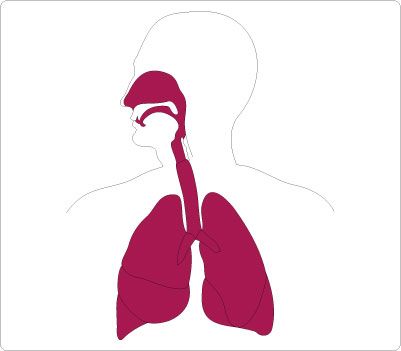

570x320 Outline Of Human Body Internal Organs

576x782 Make A Life Sized Body Activity With Life Sized Organs. This Is So

1300x1294 Human Anatomy Of The Lungs Black And White Stock Photos Amp Images